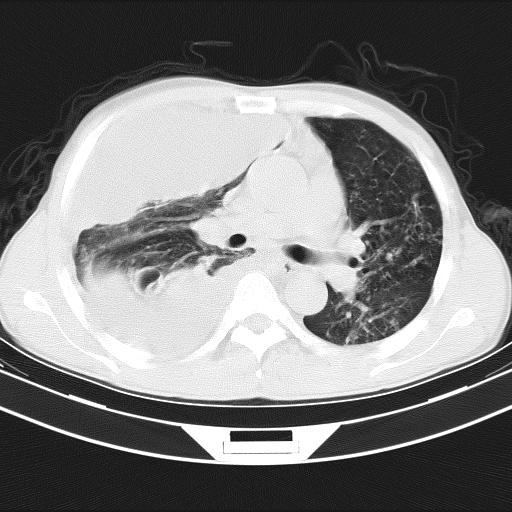

男性,44岁,结核病史多年。现胸闷气短,咳嗽,偶咳血。

1)两肺继发性肺结核伴空洞形成,左肺多发性结核球。2)右侧大量胸腔积液伴右肺部分膨胀不全。3)纵隔淋巴结肿大。

吉大一院胸水抽检结果:结核性胸水

结核性胸水——结核性胸膜炎 感谢楼主反馈结果

感谢反馈结果--结核性胸水,双肺陈旧结核。